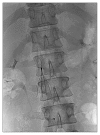

A 20-year-old man presented with a femur fracture and epidural hemorrhage (EDH) following a fall. One month after fracture surgery, swelling developed in both legs, and he was diagnosed as having a deep-vein thrombosis and pulmonary embolism. A retrievable inferior vena cava filter (IVCF) was inserted, because EDH is a contraindication to anticoagulants. Four months later, he complained of abdominal pain, and a computed tomography scan showed a fractured IVCF strut. After percutaneous removal failed 3 times, the IVCF was surgically removed by orthopedists using a portable image intensifier without cardiopulmonary bypass.